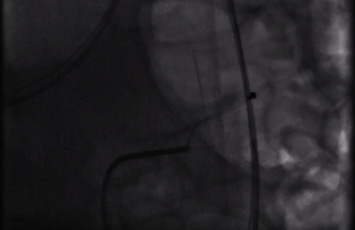

导言:异物(FB)摄入是临床实践中经常遇到的情况。大多数误食的异物通常会自行排出,无需干预。内窥镜取出异物是创伤最小的方法,只有极少的 1%需要手术干预。病例介绍。我们介绍了一例 30 岁男性的病例,他摄入了位于胃部和小肠的多个 FB。虽然通过内窥镜成功切除了胃中的 FB,但由于穿孔问题和专业知识有限,切除小肠中的第二个 FB 证明具有挑战性。考虑到患者之前曾因手术治疗导致大切口疝,医生不建议进行手术切除。因此,在外科医生和介入放射科医生(IR)的共同决定下,在 IR 技术的帮助下采用了透视引导下的切除方法:本病例凸显了在内窥镜和外科手术均不可行的情况下,采用创伤较小的替代方法的可能性。

Introduction: Foreign body (FB) ingestion represents a frequently encountered scenario in clinical practice. Most ingested FBs typically pass spontaneously, requiring no intervention. Endoscopic removal stands out as the least invasive method, with only a minimal 1% needing surgical intervention. Case Presentation. We present a case of a 30-year-old male who ingested multiple FBs located in the stomach and small bowel. While successful removal of the stomach FB was achieved through endoscopy, the second FB in the small bowel proved challenging due to perforation concerns and limited expertise. Given a history of prior surgical intervention resulting in a large incisional hernia, surgical removal was discouraged. Consequently, a collaborative decision involving surgeon and interventional radiologist (IR) led to the adoption of a fluoroscopic-guided removal approach facilitated by IR techniques.